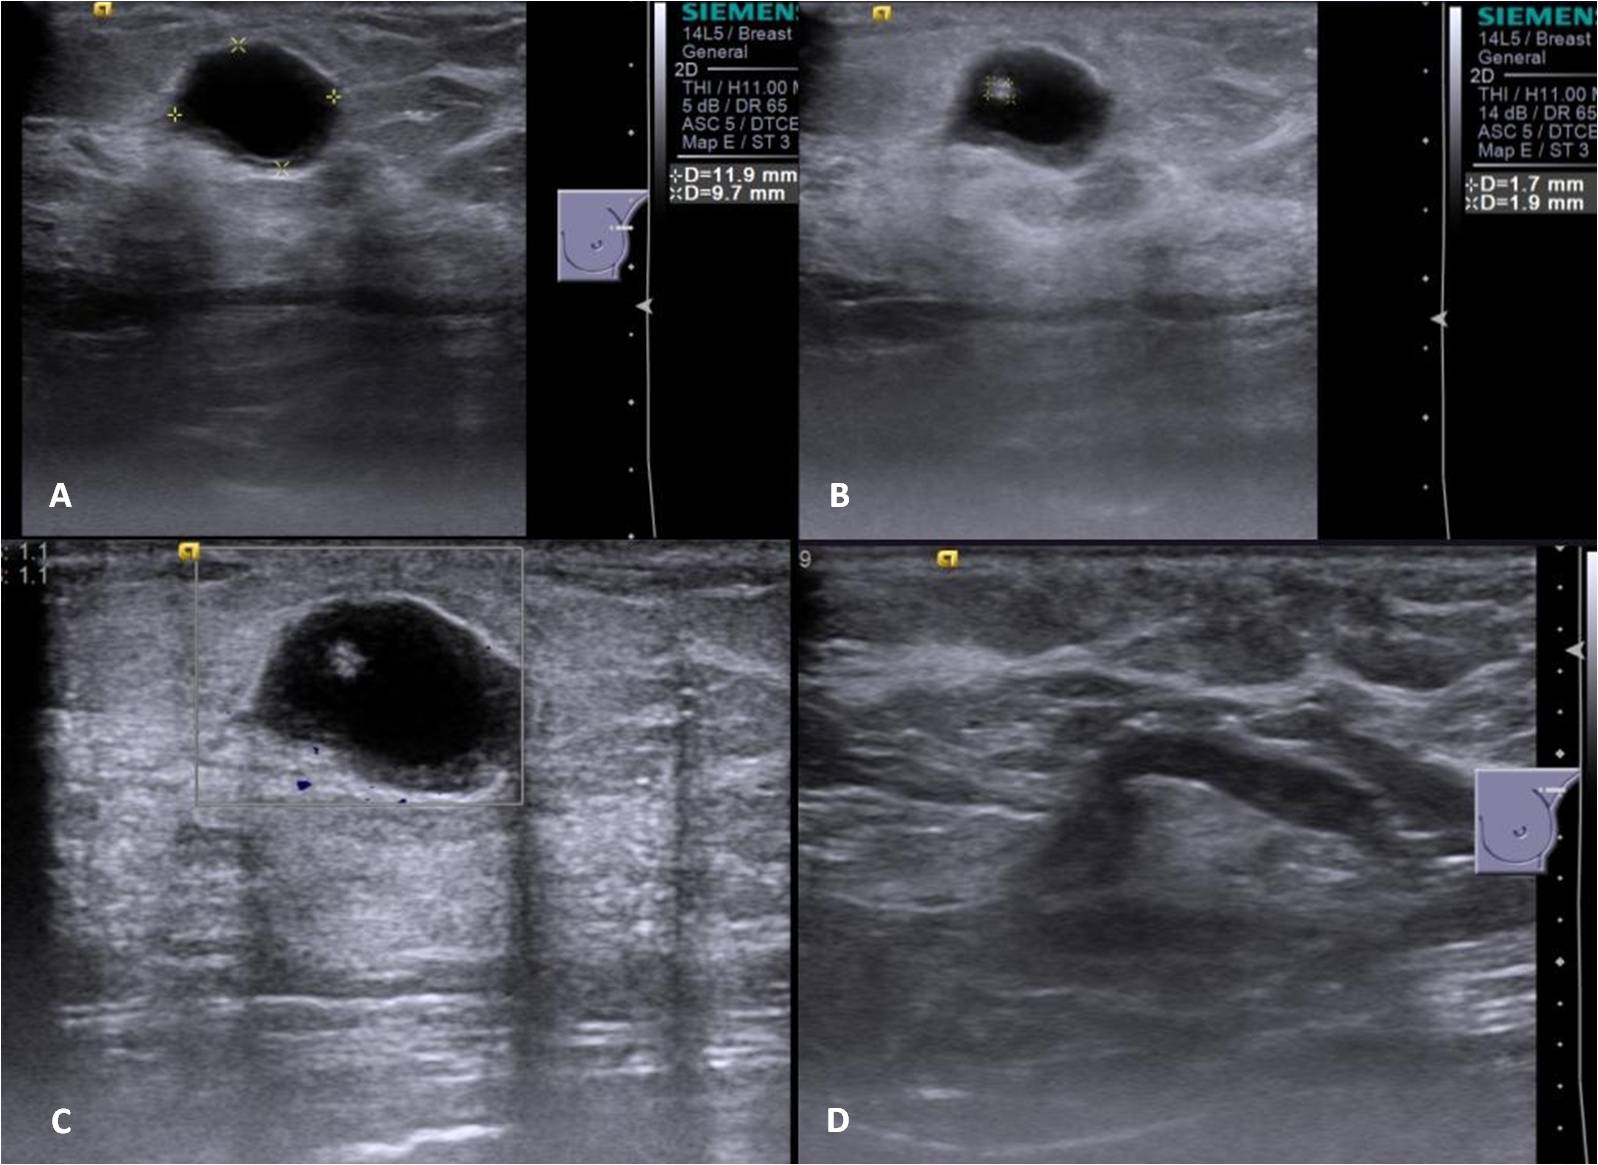

An asymptomatic 49-year old lady underwent a screening mammogram [Figure 1.]. In a background of heterogeneously dense breast parenchyma there was a 10mm round mass in the upper-outer quadrant of the left breast (anterior-third) with obscured posterior margins. No calcifications, spiculated mass or significant axillary lymph nodes were noted. She was recalled for further clinical assessment which revealed a palpable lump and an ultrasound (US) was advised. Sonomammogram [Figure 2.], in the area of mammographic abnormality, revealed a 12 x 10mm thick walled cyst with a 2mm polypoidal echogenic mural nodule arising from it’s non dependant wall. No other focal abnormality was seen in the rest of the left breast. Mildly enlarged nodes with slightly thickened cortex were noted in the left axilla. Ultrasound-guided biopsy of the complex cyst was performed [Figure 3.] with no complications. Histopathology [Figure 4] revealed larva of the cysticercal parasite (racemose cyst wall) with a surrounding giant cell reaction. Clinical follow-up after a two-month course of albendazole showed no palpable abnormality and USG [Figure 5.] in the region of abnormality showed resolution of the cyst.